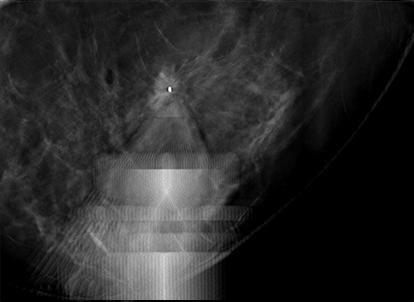

Quickly reach challenging lesion locations.

A fully integrated C-arm and bidirectional patient positioning provide a new level of 360° access to the breast, improving access to some of the most challenging lesions.1 The system features an independently rotating biopsy arm and exclusive lateral needle approach that allows clinicians to switch from a standard to lateral approach in seconds—without additional attachments and without the need to reposition the patient or acquire additional images.